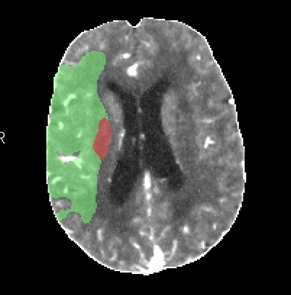

2月16日,72岁的黄先生在家中突发左侧肢体无力伴言语不清,家属将其送至我院急诊科就诊,卒中团队会诊后考虑急性脑卒中,NIHSS评分:20分,并立即护送患者至放射科。放射科医技护启动绿色通道,在3分钟内完成一站式卒中CT检查,并对脑CT灌注(CTP)及CT血管造影(CTA)图像进行快速评估:可见患者双侧颈内动脉及右侧大脑中动脉均闭塞(图1);CTP显示患者右侧大脑半球血流灌注减低(图2),但存在较大面积的缺血半暗带(图3),这提示如果能及时改善血运,可挽救大部分缺血脑组织,显著缩小脑梗死的范围,进而改善患者预后。基于可靠的影像证据,神经内科卒中团队当机立断通过急诊介入手术成功取栓并扩张颈内动脉,患者右侧大脑半球及时恢复了血供。术后第2天患者四肢、言语功能恢复良好,NIHSS评分:7分。术后第3天后MRI复查显示脑梗死范围远远小于术前低灌注区域(图4)。

图3:CTP示缺血半暗带(绿色)与核心梗死区(红色)